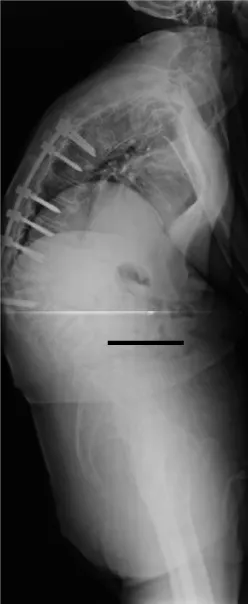

This is a retrospective study where 124 patients from January 1st, 2000 to May 31st, 2015, affected by multiple myeloma with vertebral localisation were included. All the patients were operated at a single centre by senior surgeons belonging to a single unit. Demographic details like age, sex were noted. All patients, before the surgery, were studied with standard X-ray, bone scan, CT and MRI (Figures 1,2) of the spine and location, number, type of lesions were noted. Laboratory tests including serum immunoelectrophoresis and the Bence-Jones protein urine/blood test were also done. They were clinically assessed prior to surgery and patients were divided into those presenting with only pain, radicular symptoms and neurological deficit. Visual Analogue Scale (VAS) was used and the scores were categorised into mild, moderate and severe. Written and informed consents were taken regarding the surgical procedure they underwent. Intra and post operative complications, if any, were noted.

Particularly interesting and surgically challenging was a case of G.E., male, 64 years old. In 2012 this patient underwent a stabilisation of the levels included from T7 to L3 and decompression at T8-T9 and L1-L2 for cauda equina syndrome following a pathologic fracture with cord compression. In 2014 he presented to our outpatient clinic for regular follow up with hyperkyphosis secondary to new pathologic fracture of L3, which was the level lower to the most caudal vertebra previously instrumented, associated with additional new pathologic fracture of T6, T9, hardware mobilisation, and skin decubitus ulcer. He, therefore, underwent a new surgical intervention for hardware removal, vertebroplasty at T6, T9 and L3 and consecutive L1 corpectomy, deformity correction and reconstruction of the L1 vertebral body with autologous bone graft and lateral plate T12-L2. After 12 months from the second surgery hyperkyphosis and skin ulcers in the site of hardware, decubitus were still present. We met 2 minor complications (Grade I [20,21]) not directly correlated to the surgical intervention: a transient dysphonia and a case of intraoperative hyperthermia.